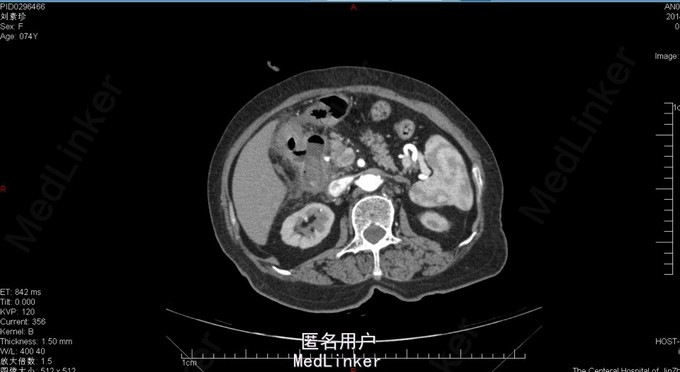

胆囊十二指肠瘘,结石性幽门梗阻

74岁女患,上腹部疼痛伴恶心呕吐3天。 3天前患者开始出现上腹部不适疼痛,同时伴有恶心、呕吐。呕吐物为胃内容物,餐后严重。患者在家自行消炎治疗,症状逐渐加重。患者为求进一步诊治来我院。 既往胆囊结石病史。

查体:上腹部压痛明显,伴反跳痛及肌紧张。 腹部ct:十二指肠内结石?(回忆部分)

胆囊十二指肠瘘,结石性幽门梗阻,腹膜炎。 给予患者胆囊切除+十二指肠修补局部引流?(记不太清)患者术后恢复还可以,顺利出院。

此病例为普外科轮转期间收集影像资料所得,病例内细致资料不全面,不能详尽分享。但此种病例少见,影像资料清晰,值得学习探讨。 欢迎普外专业同道探讨患者手术方式。让大家共同进步。